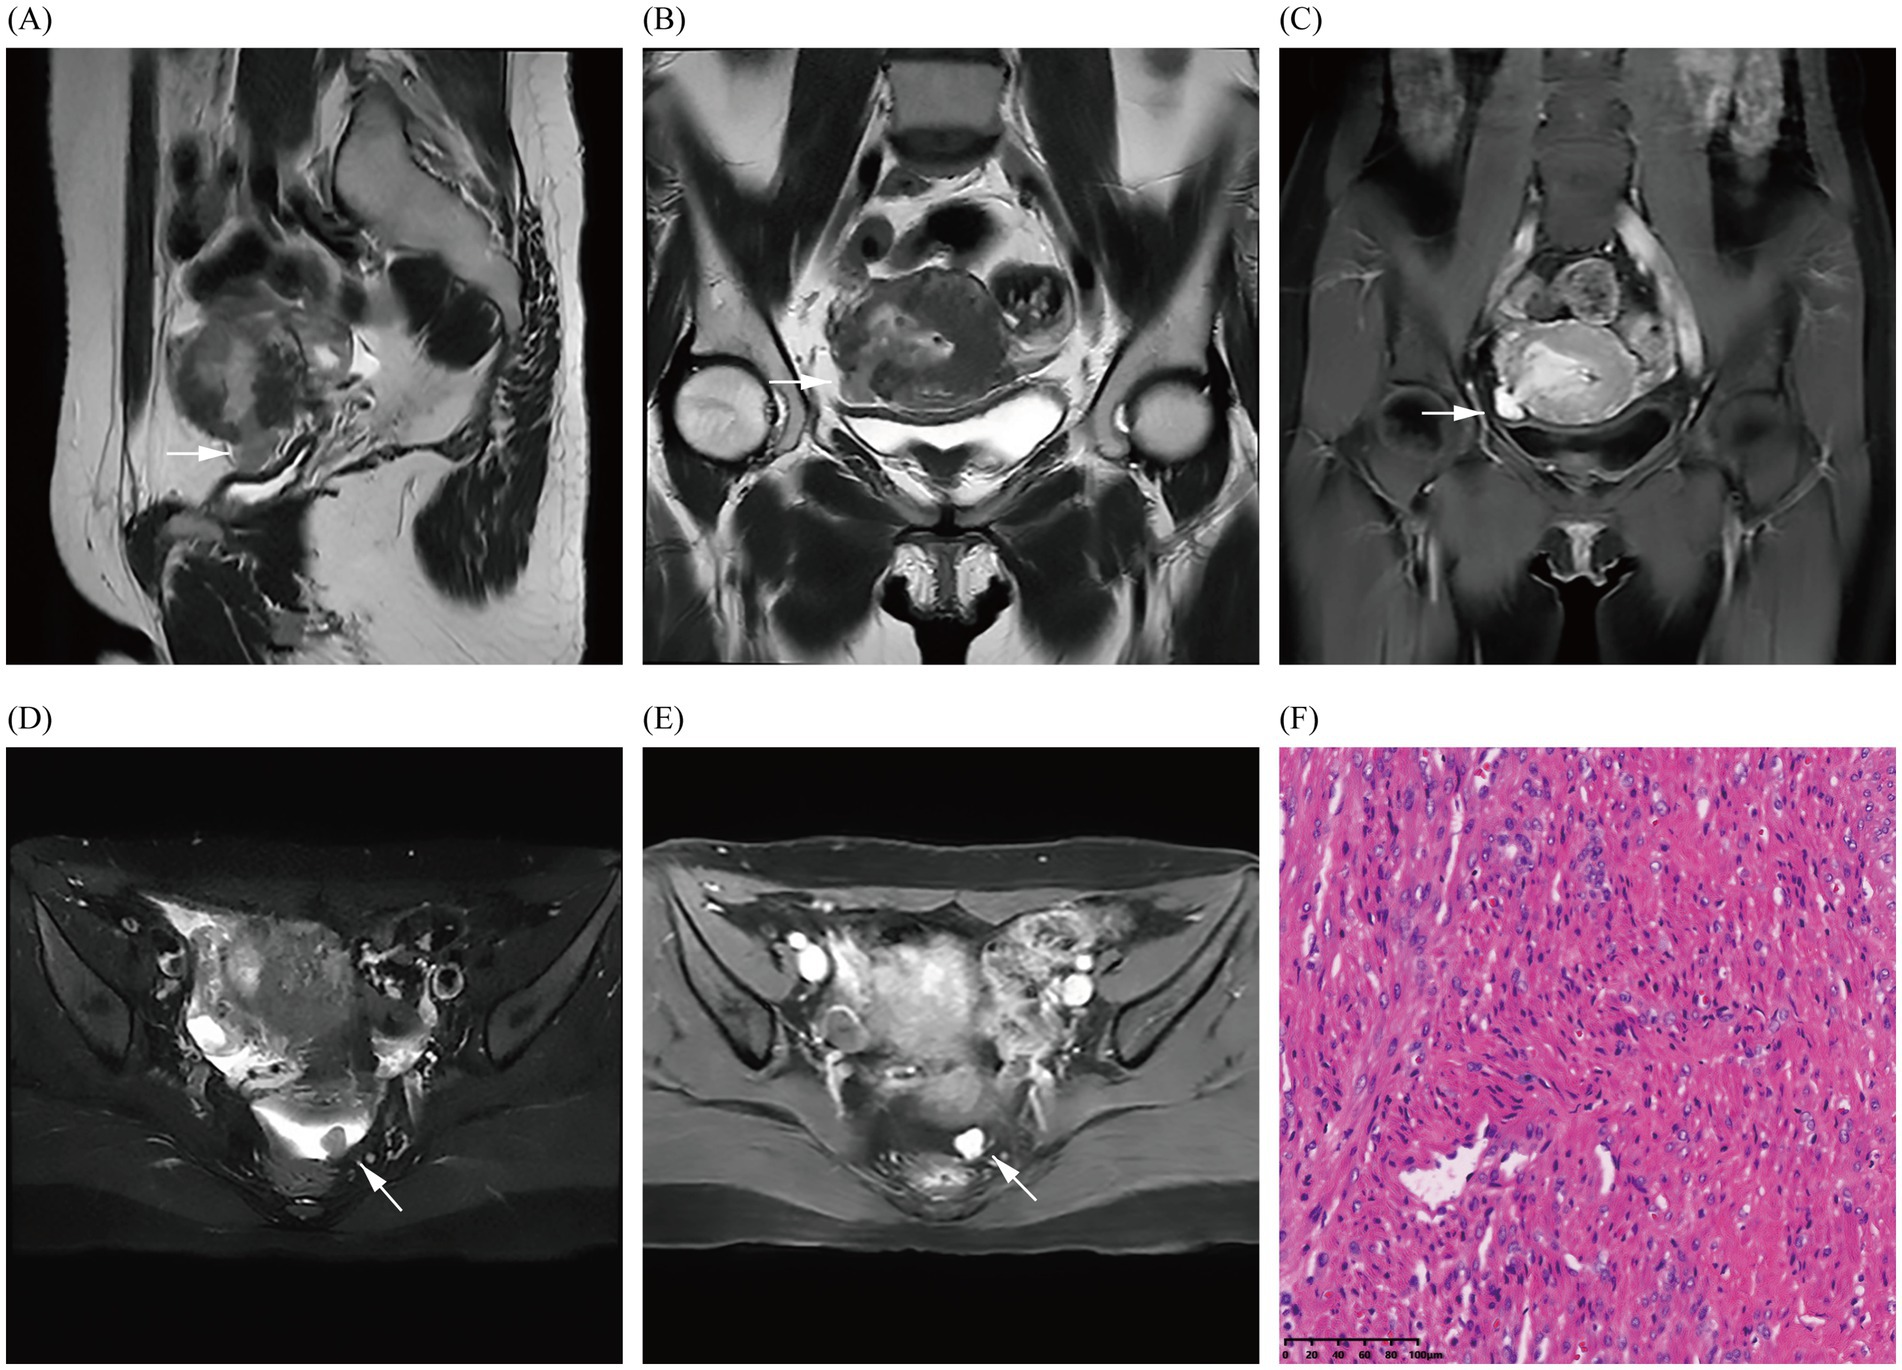

Figure 3

Images (A–E) show the MRI in October 2024 and demonstrate the fibroid breaking through the uterine serosa layer (indicated by arrows); a nodular abnormal signal shadow is also observed in the left rectouterine fossa, revealing obvious enhancement of the fibroid. Image (F) shows the pathological results (uterine and pelvic) confirming uterine leiomyoma through hematoxylin and eosin staining of the fibroid (magnification × 200).

In October 2024, the patient presented with AUB for the third time, but without dysmenorrhea, and with a heavy menstrual flow that lasted for 1.5 months and was bright red in color and moderate in volume. Laboratory tests and gynecological examination yielded normal results. TS suggested uterine hypoechoic nodules, and dynamic pelvic MRI (Figure 3) suggested the presence of a uterine myoma in the operative area (uterine fundus), locally breaching the surface of the uterine serosa and spanning the uterine cavity, myometrium, and pelvis. MRI also revealed a nodule in the left uterorectal pit, which was de novo in nature (which was in contrast to that observed under previous imaging), and based on its imaging characteristics, it was presumed to be a fibroid. Imaging revealed the presence of a utero-pelvic fistula and a nodule in the left-rectouterine fossa, which facilitated the clinician’s choice of surgical method (i.e., laparoscopic myomectomy of the uterine fibroids). During intraoperative laparoscopic exploration, the uterine appeared enlarged, and the uterine cavity revealed fibroid tumor-like tissue growth that extended to the right broad ligament; and only the uterine fibroid-like tissue identified by MRI was ultimately uncovered. The pathological results (uterine and pelvic) confirmed leiomyoma. At 5-month postoperative follow-up, the patient’s preoperative symptoms had completely resolved, and she was experiencing regular, tiny, reddish menstrual cycles without dysmenorrhea. Additionally, both transabdominal sonographies indicated no significant uterine or adnexal abnormalities.

In addition, at her recent preoperative pelvic MRI, the patient was discovered to have a small fibroid in the left rectouterine fossa that had not been detected at the time of her hysteroscopy in January 2023, approximately 3 years or more after the first laparoscopic myomectomy. When we systematically reviewed the literature, we discerned that the median size of iatrogenic parasitic myomas diagnosed after laparoscopic myomectomy was 20–50 mm, with a median time between surgery and diagnosis of 48 months; and that the myomas were often located in the abdominal cavity or port site (3). If the fibroid had been an iatrogenic parasitic myoma resulting from residual tissue debris following the first laparoscopic myomectomy, then this myoma should have been detected on the preoperative MRI performed before hysteroscopy in 2023. However, it was not detected, and we therefore propose another possibility. It is reasonable to assume that this represents a particular type of spontaneous parasitic leiomyomas. In our case, there were two differences from spontaneous parasitic leiomyomas: first, the patient had a history of laparoscopy-related surgery; and second, the main body of the fibroid was in the uterine cavity and myometrium, with a very small percentage of extra-serosal and intra-serosal localization. However, the typical growth pattern of spontaneous parasitic leiomyoma was similar to that found in our case (2). The patient’s recurrent submucosal myomas extended outward from the uterine cavity, eventually penetrating the uterine serosal layer, and portions of the myomal tissues were exposed within the pelvic cavity; some of these myomatous tissues may have lost their blood supply from the uterus and detached, subsequently only surviving via a blood supply from the peritoneum on the left side of the pelvis and eventually developing parasitic leiomyomas. To the best of our knowledge, no imaging-based literature has reported a case of a patient undergoing laparoscopic and hysteroscopic myomectomy with a recurrent submucosal fibroid that communicated with the uterine and pelvic cavities, resulting in the formation of a utero-pelvic fistula and a parasitic myoma. Furthermore, these myomas should also be differentiated from diffuse uterine leiomyomatosis (3).

The patient’s TS only suggested uterine fibroids, and we did not observe the formation of a utero-pelvic fistula, whereas MRI clearly showed the disruption of the continuity of the uterine serosa. Color Doppler hysterosonography can be used in patients with clinical suspicion of uterine fistula to observe and help clarify the presence or absence of fistula formation (8). Although it is possible to visualize uterine fistulas by injecting saline into the uterine cavity, the small ultrasonographic field of view, the restricted sound window, and the interference of gas in the intestinal lumen affect the diagnostic assessment of uterine fistulas and do not allow for the visualization of parasitic myoma. In addition, saline was not injected in routine pelvic ultrasonography. Ultrasonography also has its limitations. However, MRI images stored in Picture Archiving and Communication Systems can be accessed anytime and from anywhere, thereby facilitating communication and diagnosis between radiologists and clinicians. Moreover, pelvic MRI is valuable for postoperative follow-up, enabling the evaluation of the degree of incision healing and the location and size of recurrent fibroids. In summary, MRI can be used as a non-invasive method to clearly show uterine fistulas in multiple planes and directions (9). It also exhibits the ability to assess the peripelvic area and degree of healing of the uterine incision postoperatively, and it can assist in the clinical management of uterine fistulas by facilitating early intervention.